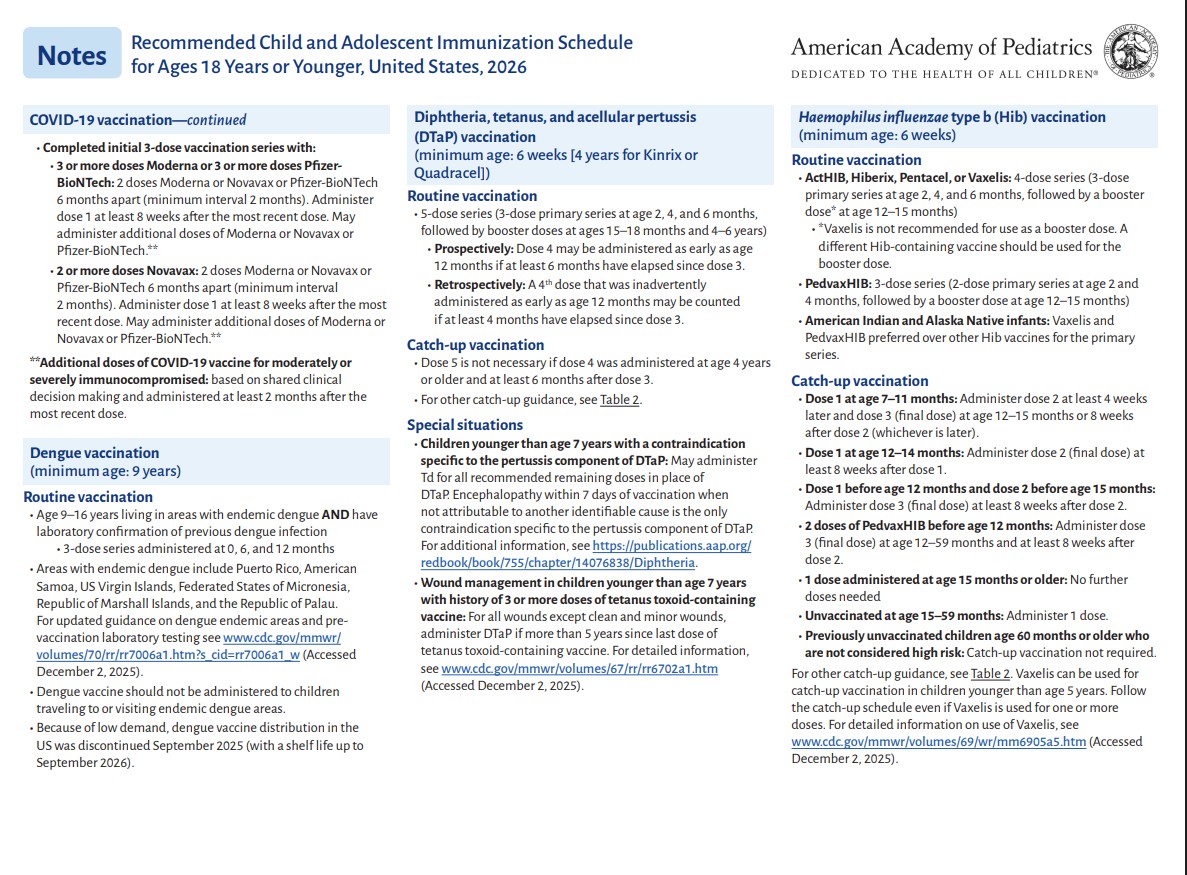

p 3